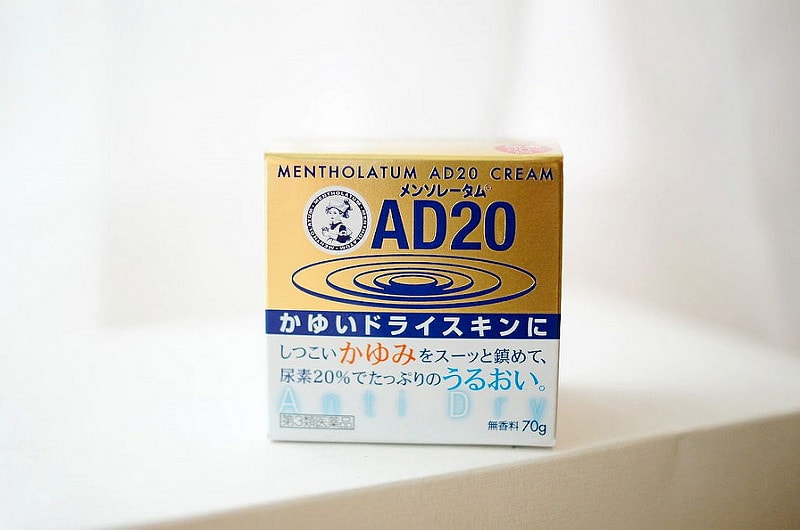

Yuskin A 悠斯晶A乳霜+金色AD20加強版~

其實這買來我也不會擦

因為我身體皮膚沒有乾燥的問題

擦一般乳液就很夠用了

這種滋潤的乳霜也是拿給家裡和長輩用

如果皮膚過敏的人是可以買來試試看